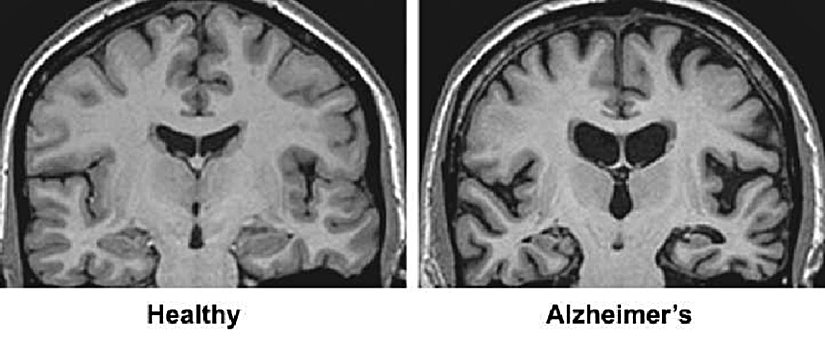

Hasar en şiddetli şekilde beyinde hafızayı kontrol eden bölgede başlar, ancak bu süreç ilk semptomlardan yıllar önce açığa çıkar. Nöron kaybı, beynin diğer bölgelerine bir miktar öngörülebilir bir şekilde yayılır. Hastalığın geç evresinde ise beyin önemli ölçüde küçülür. Araştırmacılar iki proteinin hastalık üzerinde rolüne odaklanmıştır.

Beyin Görüntülenmesi

Beyin görüntüleri artık felç, travma veya tümörler gibi bilişsel değişime neden olabilecek Alzheimer hastalığı dışındaki durumlarla ilgili gözle görülür anormallikleri saptamak için kullanılıyor. Şu anda büyük tıp merkezlerinde veya klinik deneylerde kullanılan yeni görüntüleme uygulamaları, doktorların Alzheimer'ın neden olduğu belirli beyin değişikliklerini tespit etmesini sağlayabilir.

- Manyetik Rezonans Görüntüleme (MRI) Beynin ayrıntılı görüntülerini üretmek için radyo dalgaları ve güçlü manyetik alan kullanır. MRI taramaları öncelikle diğer bulguları tespit etmek için kullanılır. Değerlendirmeler, beyin küçülmesini gösterse de, sağlanan bilgiler şu anda tanı koymaya önemli Bir değer katmıyor.